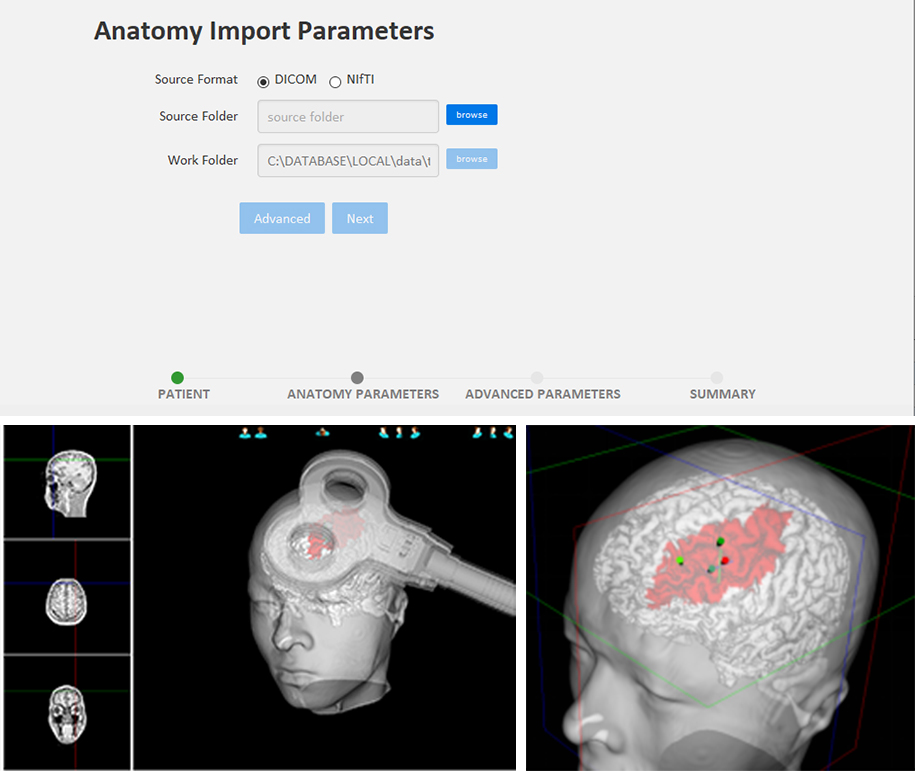

Support Common and Individua

The base software includes a standard MNI average head model brain, which satisfies TMS navigation of normal individuals with simple calibration procedure.

It can import personal MRI images, support standard DICOM, NIFTI formats, the software will automatically calculate and reconstruct the 3D model of the individual head to achieve more accurate positioning.